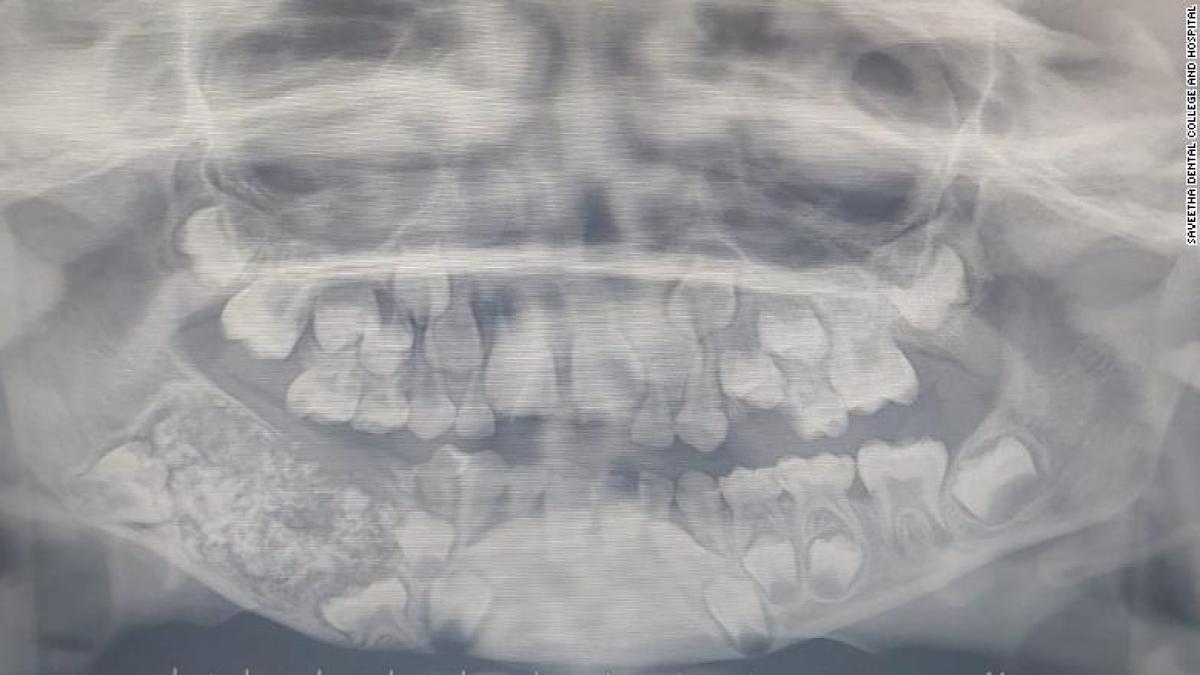

Băiețelul de șapte ani se plângea de dureri mari de obraz, așa că a fost dus la spital. După ce i s-a făcut o radiografie, medicii au încremenit. „Erau 526!” 01 Aug